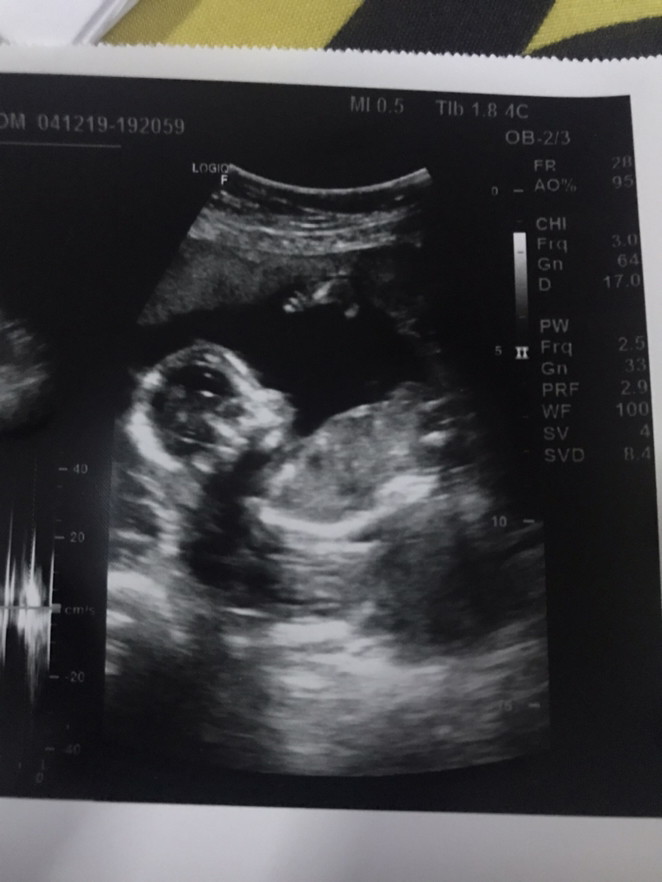

ซาวด์น้องตอน 5 เดือน

ของเราตอน 5 เดือนค่ะ